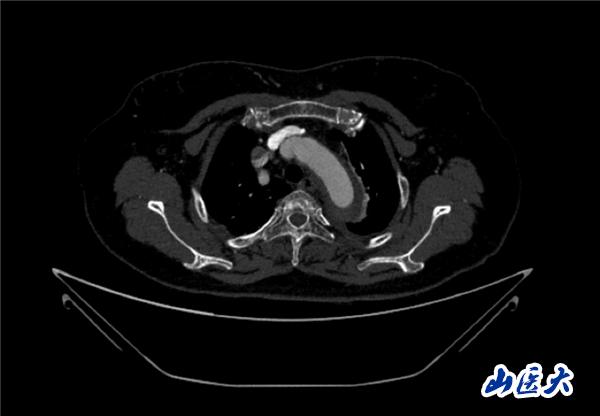

术前CTA

首例患者是一位55岁的女性,她患有高血压约2年时间,平时也会规律服用多种降压药,但血压控制始终不尽人意。2023年4月下午,她出现不明原因的头痛,在家拔罐缓解少许便未到医院就医,次日凌晨突感胸闷、胸背疼痛伴有呼吸困难等症状、家人急忙拨打了120,把患者送入医院急诊科进行救治,医生在急诊科行胸腹主动脉CTA时,显示主动脉弓部-降主动脉及腹主动脉壁间血肿,遂收治入医院血管外科,患者入院10天后复查血肿仍未有改善,依然伴有胸背部疼痛等不适,如不进一步处理,可能发展为夹层危及生命,患者及家属经过与医生团队了解沟通,决定进行创伤小、恢复快的介入手术治疗。张玮教授、符伟国教授、董红霖教授及其血管外科团队(闫盛、常文凯、田琴琴)共同商讨手术方案,最终确定使用Zipper™一体式主动脉弓覆膜支架系统,行胸主动脉覆膜支架腔内隔绝术+无名动脉、左颈总动脉、左锁骨下动脉分支重建术为患者进行治疗。董红霖教授及其血管外科团队根据患者术前头颅CT平扫提示双侧侧脑室旁缺血灶,血压控制不稳定,属夹层壁间血肿非典型夹层等风险点,制定了完整的手术方案,术中经股动脉置入Zipper支架主体,经预留导丝超选无名动脉,并确保主体支架对位准确,顺利置入左颈总动脉、左锁骨下动脉支架,重建弓上三分支。手术过程非常顺利。术后观察主动脉及分支覆膜支架定位准确;无内漏;分支支架通畅,动脉供血正常。